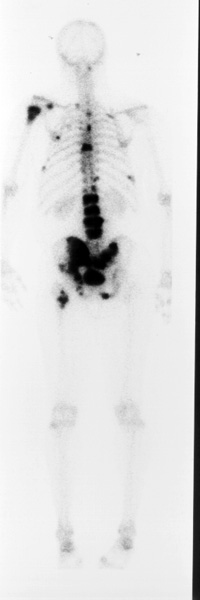

This is a 68 y/0 man with prostate

carcinoma and a PSA of 127.

Radionuclide bone imaging is the best method to survey the skeleton for evidence of metastatic spread of tumors which frequently go to bone. These tumors include breast carcinoma in women and prostate carcinoma in men. Other tumors which frequently go to bone include lung carcinoma, renal carcinoma and GI maligancies.